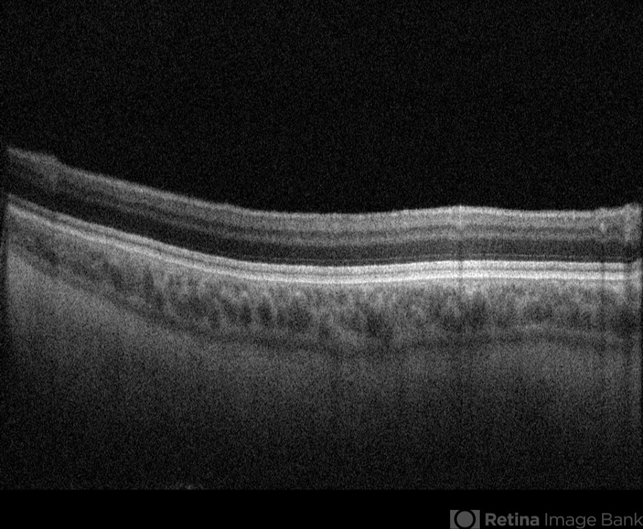

- ocular albinism

- Optical coherence tomography system

- 41 years old male came to opd with chief complaints of diminution of vision of both eyes since childhood. BCVA RE- FC 2M, LE- 6/60. On examination, patient had BE nystagmus. Fundus was tessellated with prominent choroidal blood vessels and Foveolar hypoplasia. Diagnosis of BE ocular albinism was made..